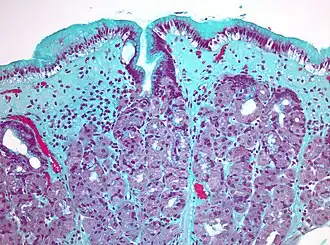

Коллагеновый гастрит, окраска трихромом Массона -